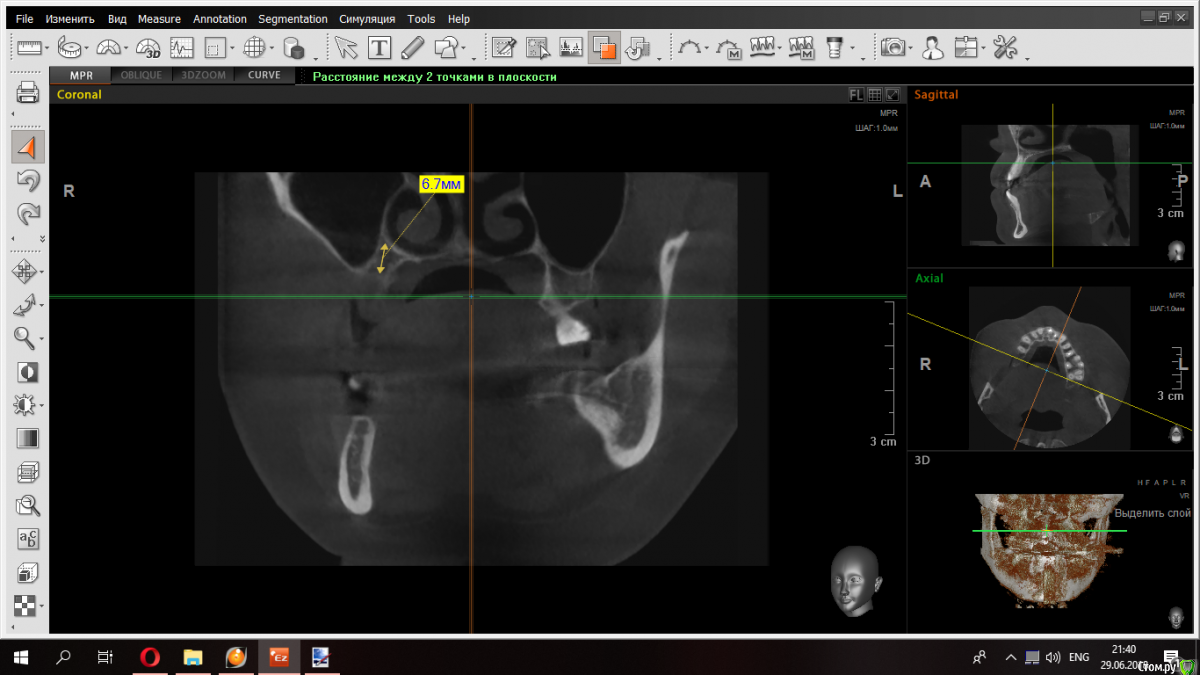

kramer Опубликовано 29 июня, 2018 Поделиться Опубликовано 29 июня, 2018 (изменено) Уважаемые коллеги, надеюсь на ваш совет по этому случаю. Какому способу аугментации вы бы отдали предпочтение? ОСЛ + НКР по вертикали с титановой сеткой? Если в области моляров еще можно было бы обойтись только синусов, то в области 15 совсем беда - ни высоты ни ширины. Срез 15Срез 16Срез 17 Изменено 29 июня, 2018 пользователем kramer Ссылка на комментарий